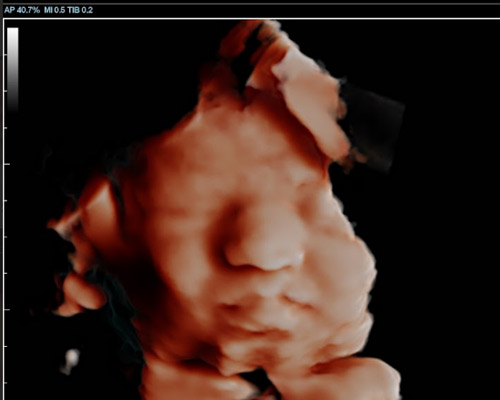

A 3D scan produces detailed still images that show the baby’s face and body in three dimensions. A 4D baby scan near Nottingham goes a step further by displaying those images in motion, allowing parents to see their baby move, stretch, or even smile.

During a 4D baby scan near Nottingham, HD Live technology creates images that appear more natural by adding light and shadow effects. This results in clearer, more lifelike visuals than traditional ultrasound images.

- Highly Detailed Images - Parents can see facial features more clearly during a 4D bonding scan.